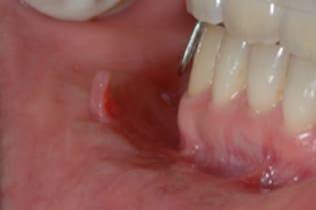

右側頬粘膜に境界明瞭な弾性硬の腫瘍を認め、線維腫を疑い腫瘍摘出術を施行した。

局所浸潤麻酔を行い、腫瘍に糸をかけ、十分にカウンタートラクションをかけた状態で、腫瘍の境界に沿ってメスで上皮を木の葉状に切開し、牽引しながらメスで周囲の結合組織と腫瘍の境界を鋭利に剥離する。切る感じではなくて削ぐ感じでメスを用いることが重要である。